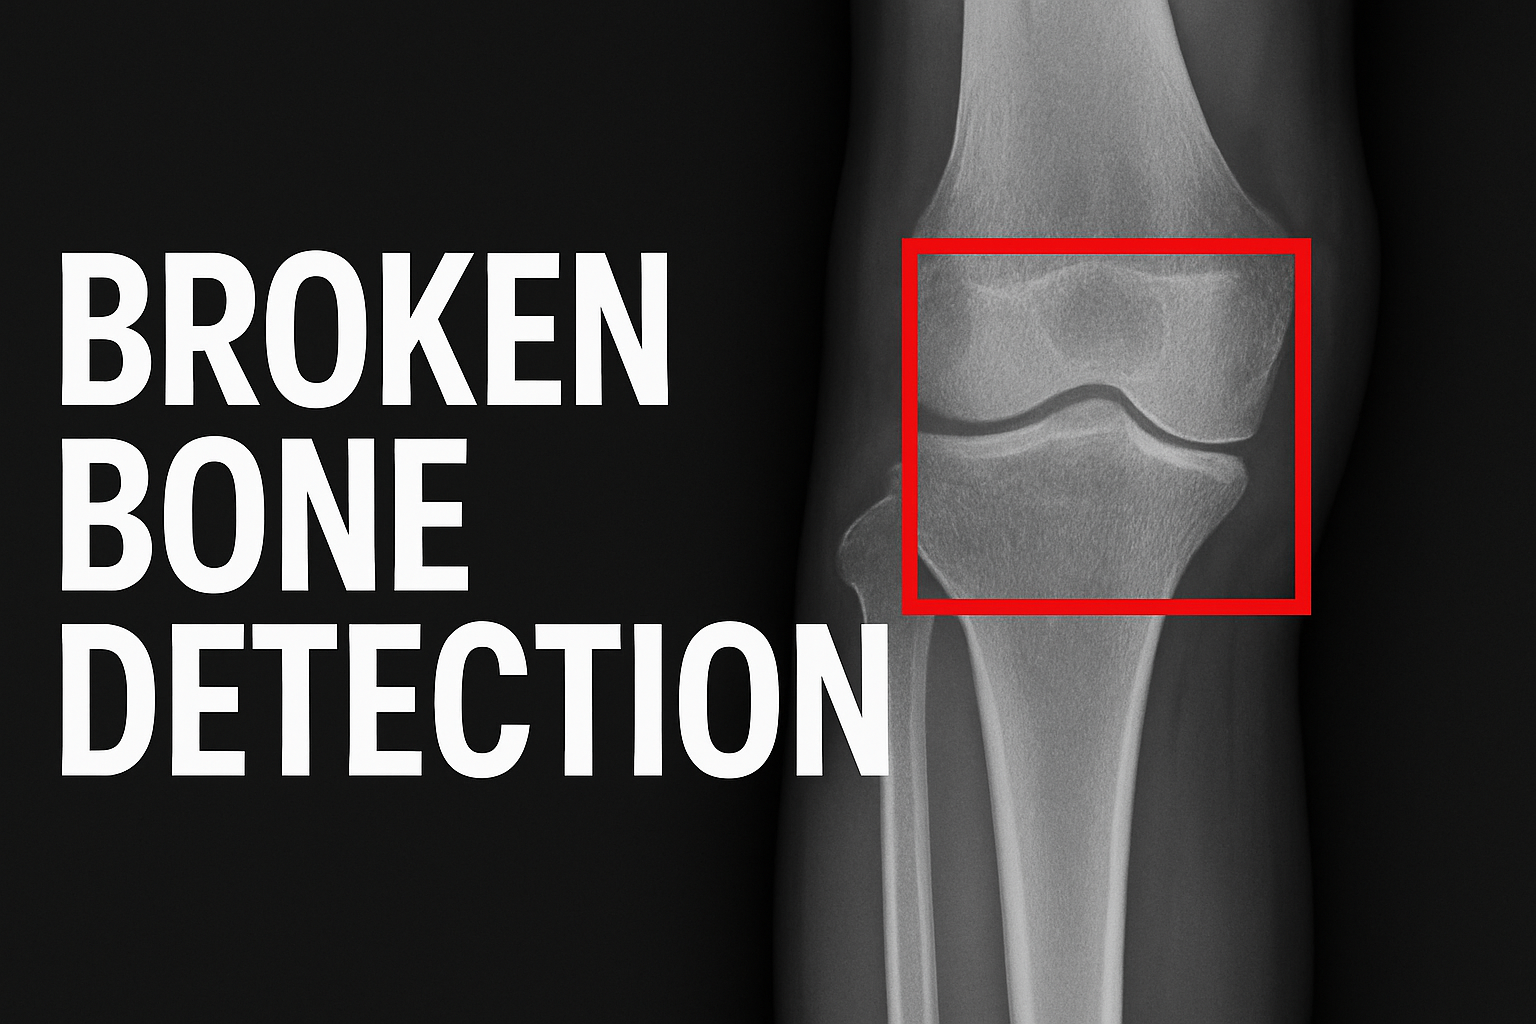

ML-based X-ray bone fracture classification system